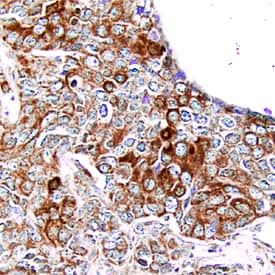

PDGF Ra antibody in Human Breast Cancer Tissue by Immunohistochemistry (IHC-P).

PDGF R alpha in Human Breast Cancer Tissue.

PDGF Ra was detected in immersion fixed paraffin-embedded sections of human breast cancer tissue using Mouse Anti-Human PDGF Ra Monoclonal Antibody (Catalog # MAB322) at 25 µg/mL overnight at 4 °C. Tissue was stained using the Anti-Mouse HRP-DAB Cell & Tissue Staining Kit (brown; Catalog # CTS002) and counterstained with hematoxylin (blue). Specific staining was localized to epithelial cells. View our protocol for Chromogenic IHC Staining of Paraffin-embedded Tissue Sections.